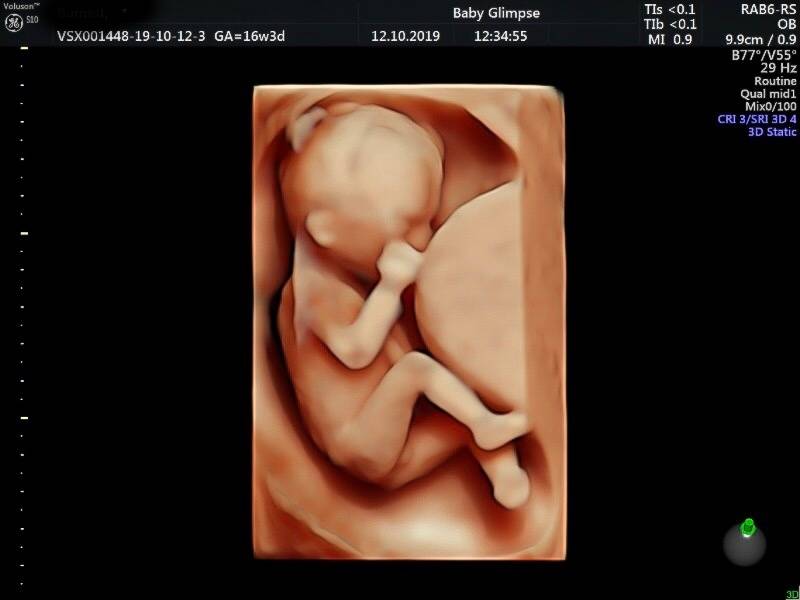

Wij maken jouw kennismaking magisch

Zwanger zijn is iets magisch. En dat prachtige gevoel willen wij nastreven in onze praktijk. Onze echoscopisten hebben een verloskundig achtergrond en werken daarnaast met de beste apparatuur. Ook hebben wij de leukste samenwerkingen met de mooiste merken waar jullie van kunnen profiteren. Dit alles zorgt voor een geweldige ervaring. Tot snel bij Baby Glimpse…